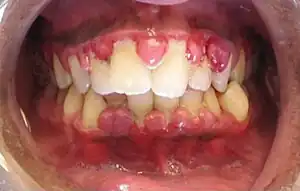

| Gingivitis, a common cause of inflammatory gingival enlargement. | |

Inflammatory enlargement

Gingival enlargement has a multitude of causes. The most common is chronic inflammatory gingival enlargement, when the gingivae are soft and discolored. This is caused by tissue edema and infective cellular infiltration caused by prolonged exposure to bacterial plaque, and is treated with conventional periodontal treatment, such as scaling and root planing.[1]

Drug-induced enlargement

This type of gingival enlargement is sometimes termed "drug induced gingival enlargement" or "drug influenced gingival overgrowth",[6] abbreviated to "DIGO".[7] Gingival enlargement may also be associated with the administration of three different classes of drugs, all producing a similar response:[8] Gingival overgrowth is a common side effect of phenytoin, termed "Phenytoin-induced gingival overgrowth" (PIGO).[9]

Of all cases of DIGO, about 50% are attributed to phenytoin, 30% to cyclosporins and the remaining 10-20% to calcium channel blockers.

Drug-induced enlargement has been associated with a patient's genetic predisposition,[11] and its association with inflammation is debated. Some investigators assert that underlying inflammation is necessary for the development of drug-induced enlargement,[12] while others purport that the existing enlargement induced by the drug effect compounds plaque retention, thus furthering the tissue response.[13] Careful attention to oral hygiene may reduce the severity of gingival hyperplasia.[14] In most cases, discontinuing the culprit drug resolves the hyperplasia.[14]